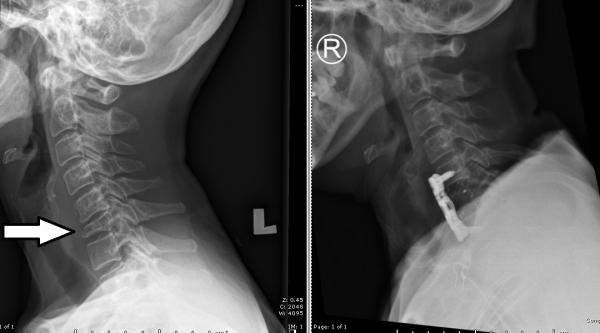

照了X光后,证实了是第6节颈椎崩塌,压迫神经线,导致疼痛和手指麻痺无力。方太只有58岁,不太可能因为骨质疏松症造成颈椎崩塌,据我判断,骨转移的可能性更大。

为免误伤神经系统,手术全程以电脑导航进行,先切除崩塌的椎骨,再植入钛合金螺丝,固定和支撑第5至第7节颈椎。历时5小时的手术顺利完成,术后情况稳定,但因为手术刀穿过声带旁直达颈椎,所以声音呈现暂时性的沙哑,随着伤口复原,即可自行改善。